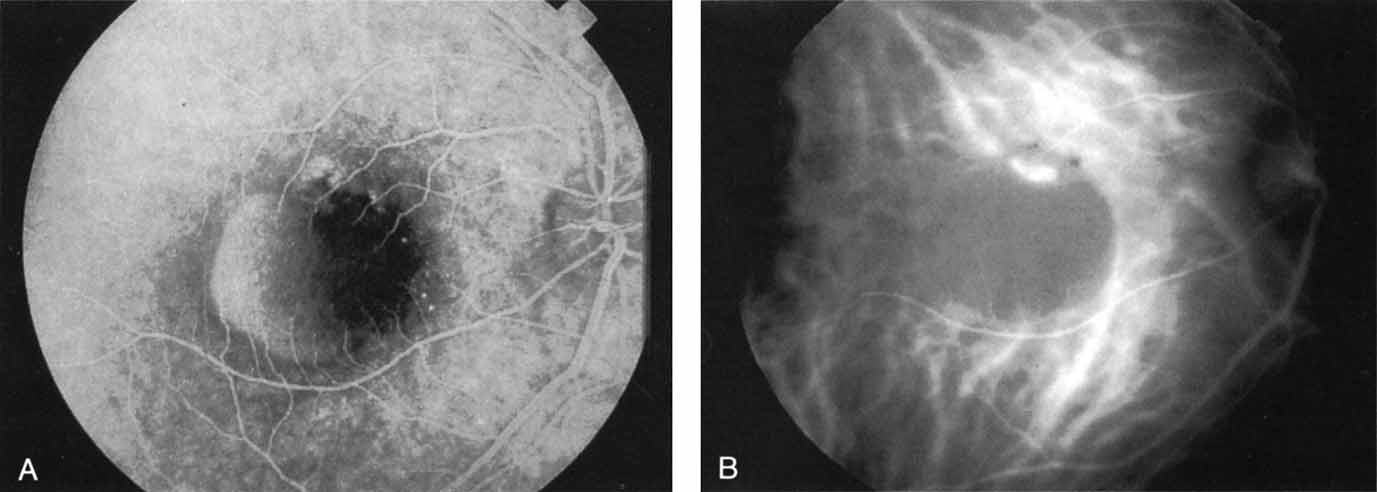

Most promising in this category of inflammatory choroidopathies is a better detection and understanding of the lesions of multifocal choroiditis. Multiple large, scattered, hypofluorescent spots are seen on ICG angiography, particularly in the later phases of the angiogram69 (Fig. 18). These lesions are not evident either on clinical examination or on fluorescein angiography. In addition to having these larger hypofluorescent lesions, patients with multifocal choroiditis have smaller dot-like lesions and hyperfluorescent foci that do not correlate with lesions seen clinically or by FA. They involve the posterior pole and in some patients extend into the mid-periphery. There is also a “papillotropic” involvement, with confluent hypofluorescent lesions surrounding the optic nerve,69 which may be useful in understanding the associated blind-spot enlargement evident in this condition.70 Other zonal visual field defects have been associated with this condition,70 and corresponding ICG abnormalities have been documented in some patients.69

Fig. 18 A. Clinical photograph of a patient with active inflammation associated with multifocal choroiditis. An atrophic scar from previous laser photocoagulation treatment is noted in the temporal macula. The patient reported visual disturbance, and an enlarged blind spot was noted on visual field testing. B. Late-phase indocyanine green study demonstrating a multitude of hypofluorescent spots that were larger than those seen with multiple evanescent white dot syndrome and more numerous and more extensively distributed than appreciated on clinical examination. Note that there is marked confluence of these lesions around the optic nerve, which may help to explain the enlarged blind spot noted on visual field testing.

Natural history data indicate that with progressive increase in vitritis and associated choroidal inflammation, an increase in the number and extent of these hypofluorescent lesions can be documented.40 Furthermore, use of oral steroid therapy as a means of controlling this inflammatory process has been documented to produce not only clinical resolution of the inflammatory process but also corresponding resolution of the hypofluorescent lesions seen on ICG angiography.69 These clearly demonstrated lesions not only may lead to a better understanding of the process of inflammation involved in multifocal choroiditis and potential management strategies but also may serve to differentiate this condition from the ocular histoplasmosis syndrome.